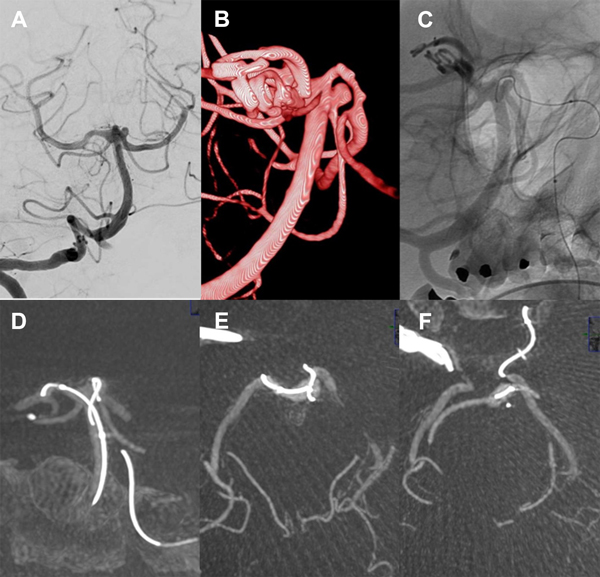

Figura 8. Paciente 18, caso 19. A, B: proyecciones AP y OAD de angiografía convencional y 3D, mostrando un aneurisma tipo BA- SCA izquierdo; C: Fluoroscopía en OAD, abordaje desde PComA izquierda procurando llegar a SCA  izquierda para implante de stent; D: proyección similar en XperCT; E-F: proyección axial de XperCT comprobando situación de microguía fuera de la silueta de arteria basilar, atrapada en vaso perforante.

Mujer de 71 años con historia de hipertensión arterial  y aneurismas cerebrales múltiples, tratamiento quirúrgico de aneurisma de comunicante posterior derecho dos meses atrás. Convulsiones tratadas con Levetiracetam. En acuerdo con Neurocirugía se propone tratamiento endovascular de un aneurisma de cerebelosa superior izquierda.

Con la paciente bajo anestesia general  y desde punción femoral bilateral se colocan introductores 6 y 5F.  Se realizan angiografías preembolización desde vertebral derecha dominante demostrando un tope basilar algo displásico. Entre la cerebral posterior y la cerebelosa izquierdas se observa un aneurisma redondeado algo irregular de 3 x 3.5 mm, cuello 3 mm (AR 1.2, DNR 1) desde cuyo margen inferior (proximal) tiene origen la arteria cerebelosa superior. Las cerebrales posteriores están permeables y es visible la comunicante posterior izquierda por inyección desde carótida izquierda.

Se colocan entonces catéteres guías 5F en vertebral derecha y 6F en carótida interna izquierda, planeando un doble abordaje similar al caso 3 presentado arriba, con stenting desde SCA izquierda a segmento P1 izquierdo y microcatéter “jailed” para implantar coils.

Se navega el sifón carotídeo izquierdo y la comunicante posterior y desde ésta en forma retrógrada por cerebral posterior izquierda hacia P1 y tronco basilar utilizando microcatéter SL10 y microguías primero Transend 14 y luego Mirage 0.008” para navegación más delicada, procurando llevarlo a la SCA para implantar un stent Neuroform Atlas.

El SL10 requiere reposicionamiento ya que el tope basilar dilatado dificulta el cateterismo selectivo de la arteria cerebelosa superior izquierda. Para ello se utiliza además de la guía Mirage el agregado de un microbalón Hyperform desde vertebral derecha que es inflado parcialmente en el tope basilar, para formar una contención lateral que permita al cateterismo selectivo de la arteria cerebelosa.

En estas maniobras de reposicionamiento y abordaje con la microguía hacia el origen de la arteria cerebelosa, se nota en un momento la limitación de movimiento del extremo distal de la microguía que no permite retirarla, observando  una posición fija del extremo distal de la guía. Ante esta situación inusual se realiza una XperCT que muestra el extremo de la microguía externo y posterior a la silueta de la arteria basilar, sin observar signos de disección; en cambio, impresiona que el extremo de la microguía se insinúa en una rama perforante muy delgada.

A pesar de las instilaciones de vasodilatadores desde catéter y microcatéter, la microguía permanece atrapada y no se logra retirar tras unas dos horas de intervención,  por lo que se decide dejarla emplazada en el lugar retirando el microcatéter. Los controles angiográficos muestran sólo irregularidad a nivel del segmento P1 izquierdo e indemnidad del resto de los vasos. La tomografía computada realizada con el angiógrafo descarta extravasación.

La paciente se recupera de la anestesia somnolienta, movilizando los cuatro miembros y con respuesta verbal y se traslada a Cuidados Intensivos. Controles posteriores con TAC helicoidal no demostraron infarto (figura 8).